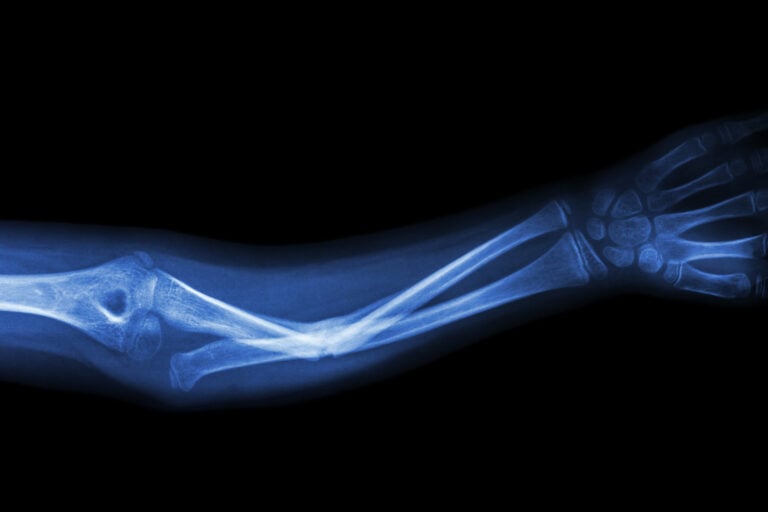

What Is a Bone Fracture Injury?

Bone fractures occur when there is a break, crack, or splintering in the bone. These injuries can range from hairline fractures that heal with rest to complex, compound fractures requiring surgery and long-term rehabilitation. Fractures are typically caused by: